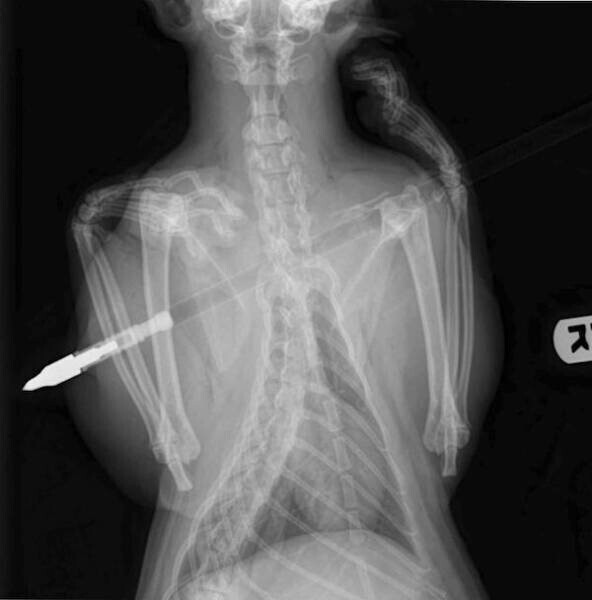

5. Стріла